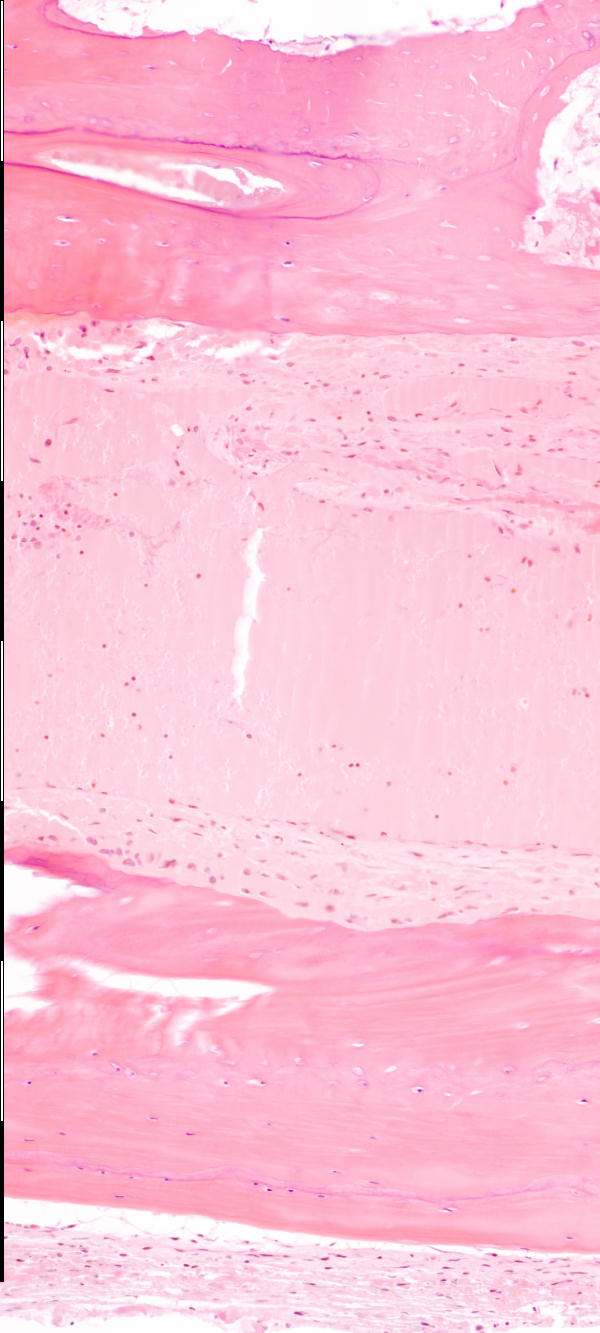

Medium magnification of immature bone from the vault